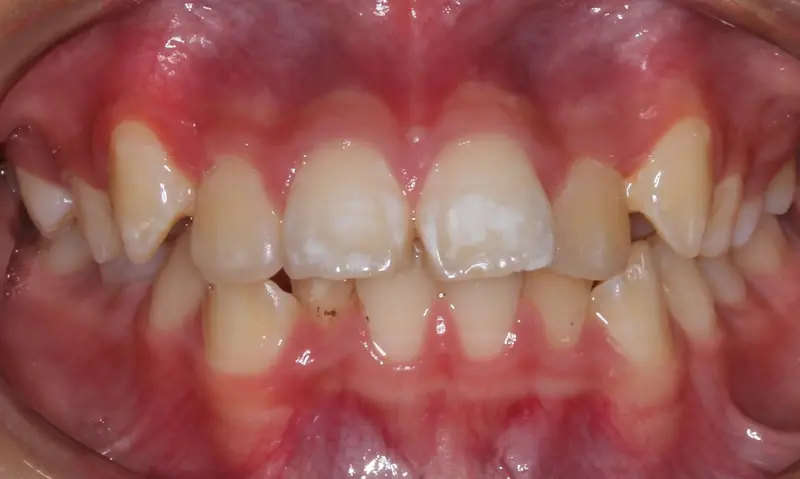

The Diagnosis

Severe crowding with blocked-out permanent teeth. The jaw size was insufficient to accommodate the erupting adult teeth, leading to significant rotation and displacement.

The Engineering

By intervening early, we utilized rapid palatal expansion to develop the arch width. This created the necessary space for the permanent teeth to erupt naturally, avoiding the need for future extractions.